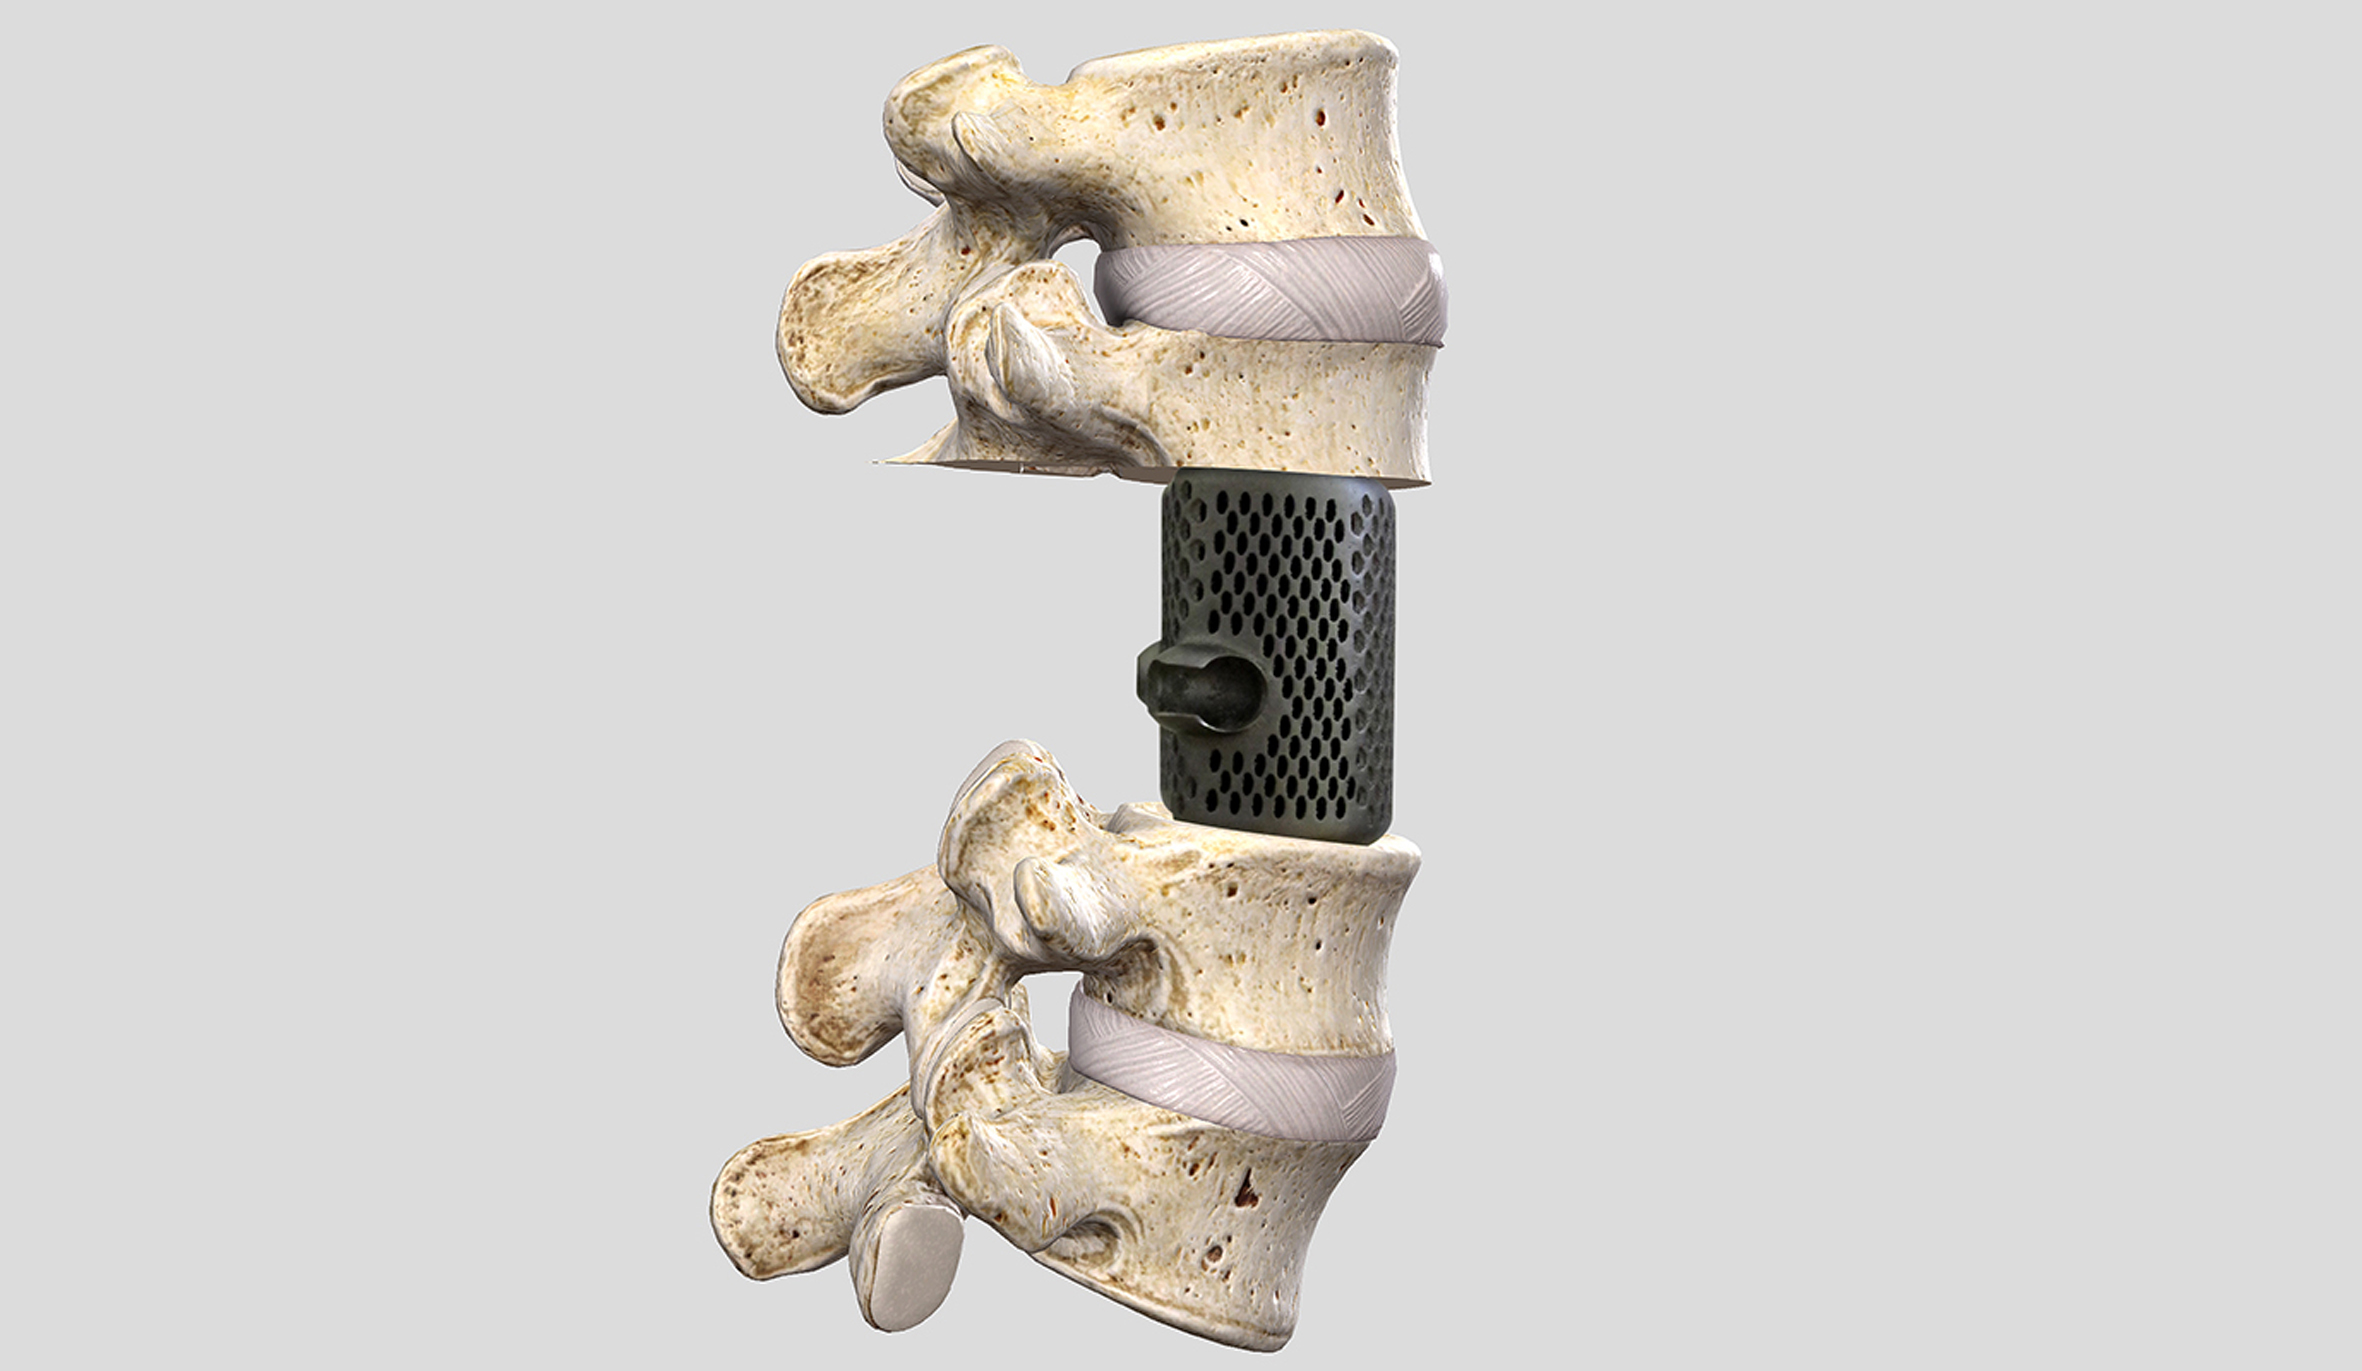

Patologie oncologiche della colonna (tumori primitivi, metastasi, fratture patologiche).

Patologie degenerative della colonna (ernia del disco; discopatia degenerativa, stenosi del canale vertebrale, scoliosi degenerativa dell’adulto).